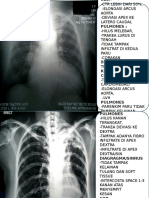

YTH TS :

Hasil pemeriksaan Thorax PA:

- Corakan bronchovascular normal

- Tidak tampak proses spesifik aktif dan lesi –lesi noduler kedua paru

- COR : CTI dalam batas normal, Aorta normal

- Kedua sinus dan diafragma baik

- Tulang-tulang intak

Kesan : Foto Thorax dalam Batas Normal